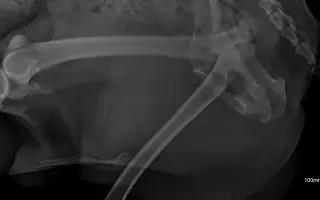

Pomozte Dirkovi změnit tento příběh